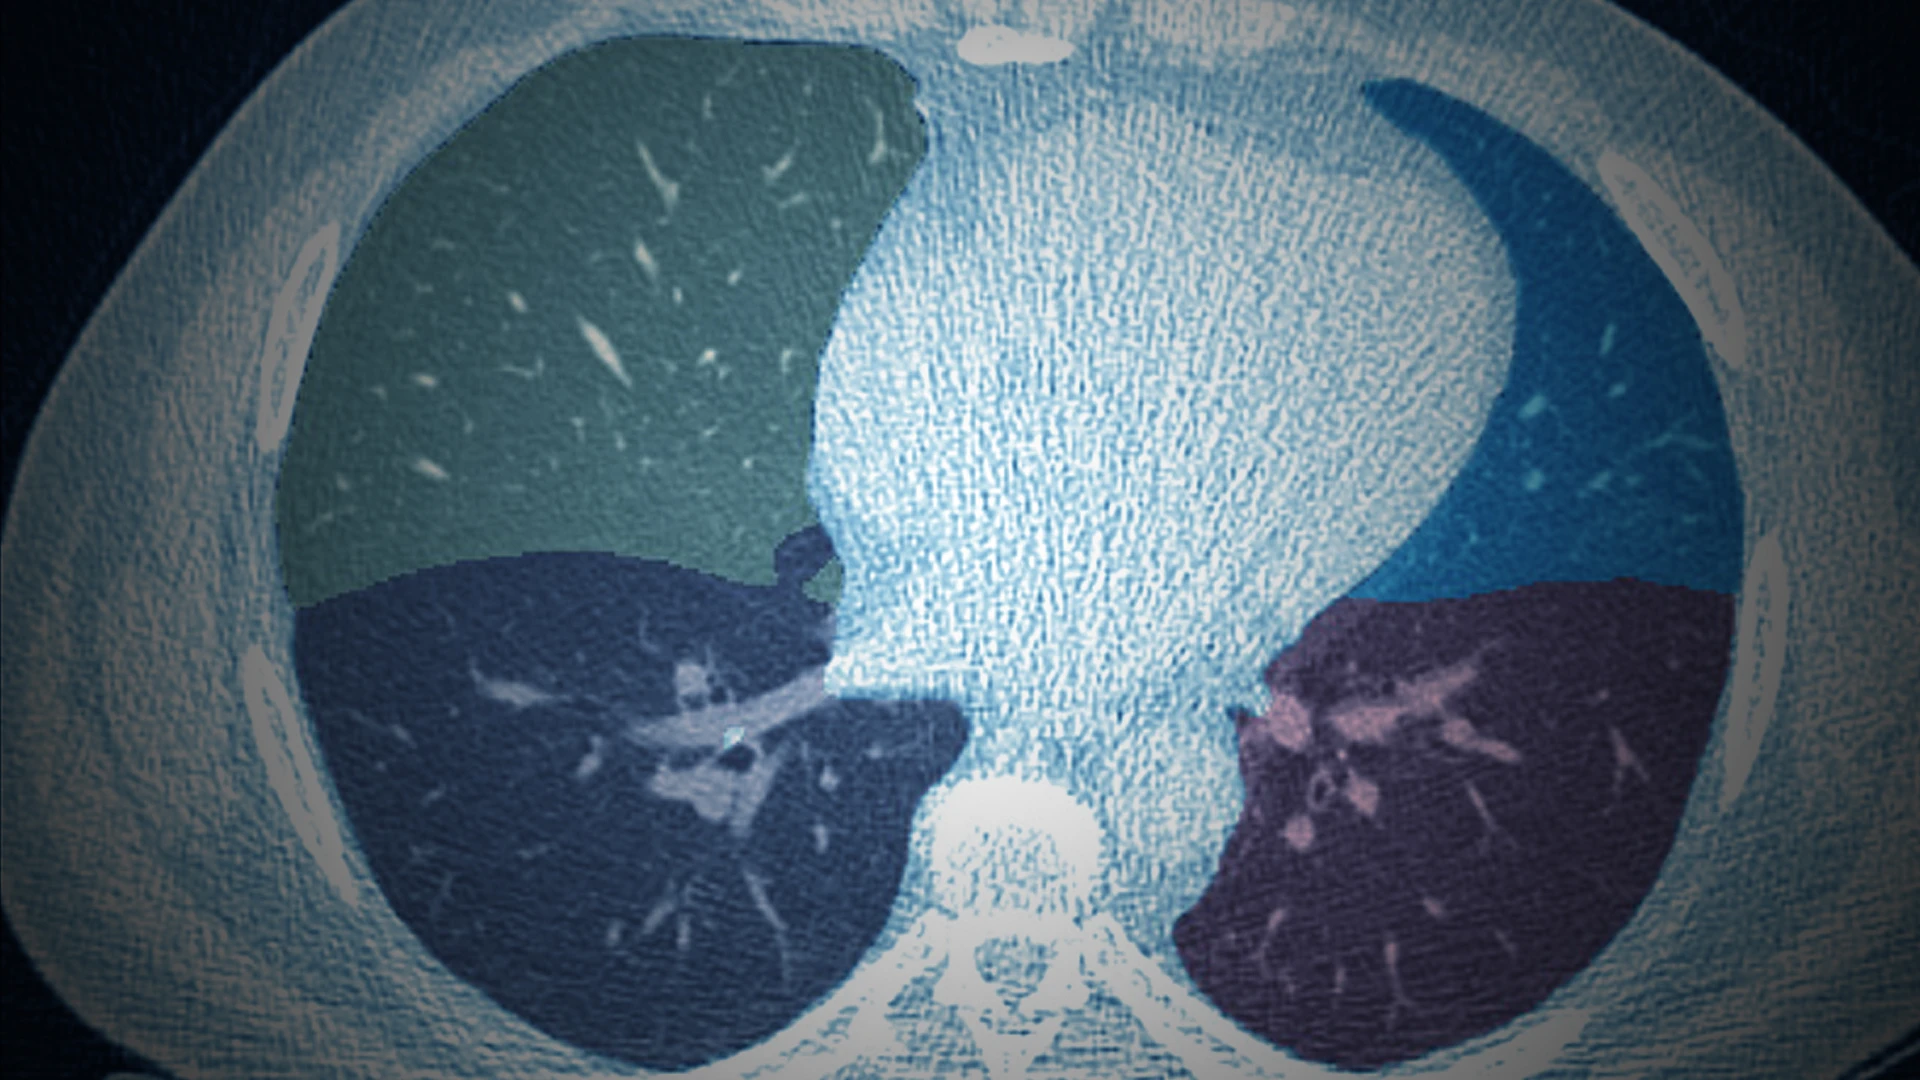

AIRS can also be applied to LDCT scans for disease assessments beyond lung cancer, as described in the Journal of Thoracic Imaging paper.

Other AI-enabled applications from a single low-dose chest scan include muscle and fat distributions, alcoholic liver disease, nonalcoholic liver disease, hepatic cancers, metabolic disorders, and pancreatic and kidney cancers. Pancreatic cancer is more deadly than lung cancer, but early detection has been shown to greatly increase survival.